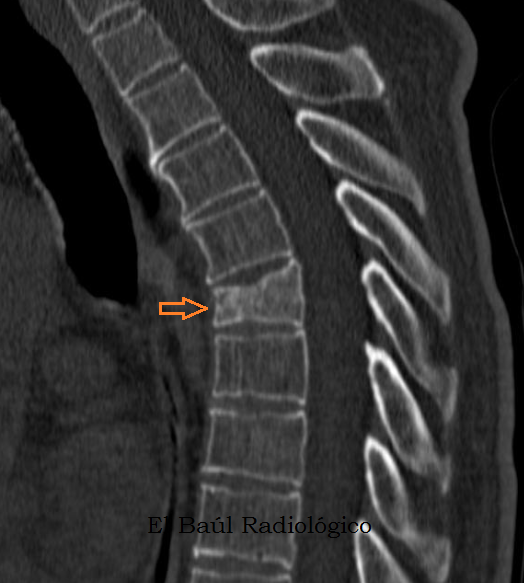

El Baúl Radiológico: APLASTAMIENTOS VERTEBRALES: PAUTA DIAGNÓSTICA

WebEn términos generales, la incapacidad permanente causada por una fractura de húmero puede variar entre el 5 y el 20 por ciento. Esto significa que, dependiendo del lugar y la. WebLa incapacidad por fractura de tobillo depende de la gravedad de la lesión. En general, las fracturas menores no producen una incapacidad permanente, pero sí pueden restringir. WebLa incapacidad permanente total. En determinados casos, podrá instarse la incapacidad permanente total por discopatía degenerativa. Nos referimos a casos en los. WebConcepto de aplastamiento vertebral. “Entendemos por aplastamiento vertebral aquella pérdida de altura de la parte anterior del cuerpo vertebral o de su porción central en al. WebIncapacidad por artrosis. Si quieres conseguir una paga o pensión por invalidez, discapacidad o incapacidad permanente por artrosis, ¡podemos ayudarte!. Estos son. Web¿Se puede solicitar una pensión de incapacidad por lesiones de espalda? Extracto de la entrada: En este post vamos a hablar sobre las posibilidades que pueden. WebIncapacidad permanente por Distrofia Simpática Refleja. La Distrofia Simpática Refleja puede ser merecedora de una pensión de incapacidad permanente, aunque quien lo.

Web¿Se puede solicitar una pensión de incapacidad por lesiones de espalda? Extracto de la entrada: En este post vamos a hablar sobre las posibilidades que pueden. WebIncapacidad permanente por Distrofia Simpática Refleja. La Distrofia Simpática Refleja puede ser merecedora de una pensión de incapacidad permanente, aunque quien lo. WebLas fracturas por compresión vertebral (FVC) se producen cuando el bloque óseo o cuerpo vertebral de la columna vertebral se colapsa, lo que puede provocar dolor.